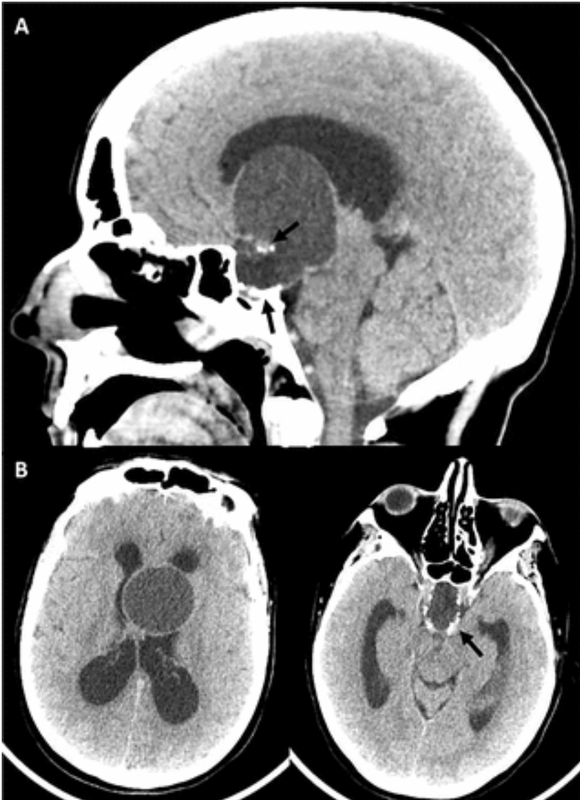

?患者女性,40歲。頭痛反復發(fā)作8年,檢查發(fā)現(xiàn)鞍區(qū)鞍上占位入院。????術前一般情況可,視力視野檢查正常。術前MR提示:鞍區(qū)鞍上第三腦室內(nèi)外囊實性占位。腫瘤已完全占據(jù)第三腦室前部,上方達兩側(cè)室間孔。側(cè)方擠壓腦室壁,和下丘腦區(qū)域關系密切,后方擠壓中腦。考慮顱咽管瘤。CT提示腫瘤部分鈣化。????采取內(nèi)鏡經(jīng)鼻入路顱咽管瘤切除術。術中見腫瘤起源于垂體柄近端、下丘腦區(qū)域。術前影像所見的鈣化部分,大大提升了手術難度,好在沒有重要血管及穿支在鈣化灶內(nèi)穿行,仍能全切腫瘤。????術后患者恢復良好,術后3天復查核磁提示腫瘤全切。術后病理:成釉質(zhì)細胞型顱咽管瘤。(江蘇省人民醫(yī)院神經(jīng)外科陶超)